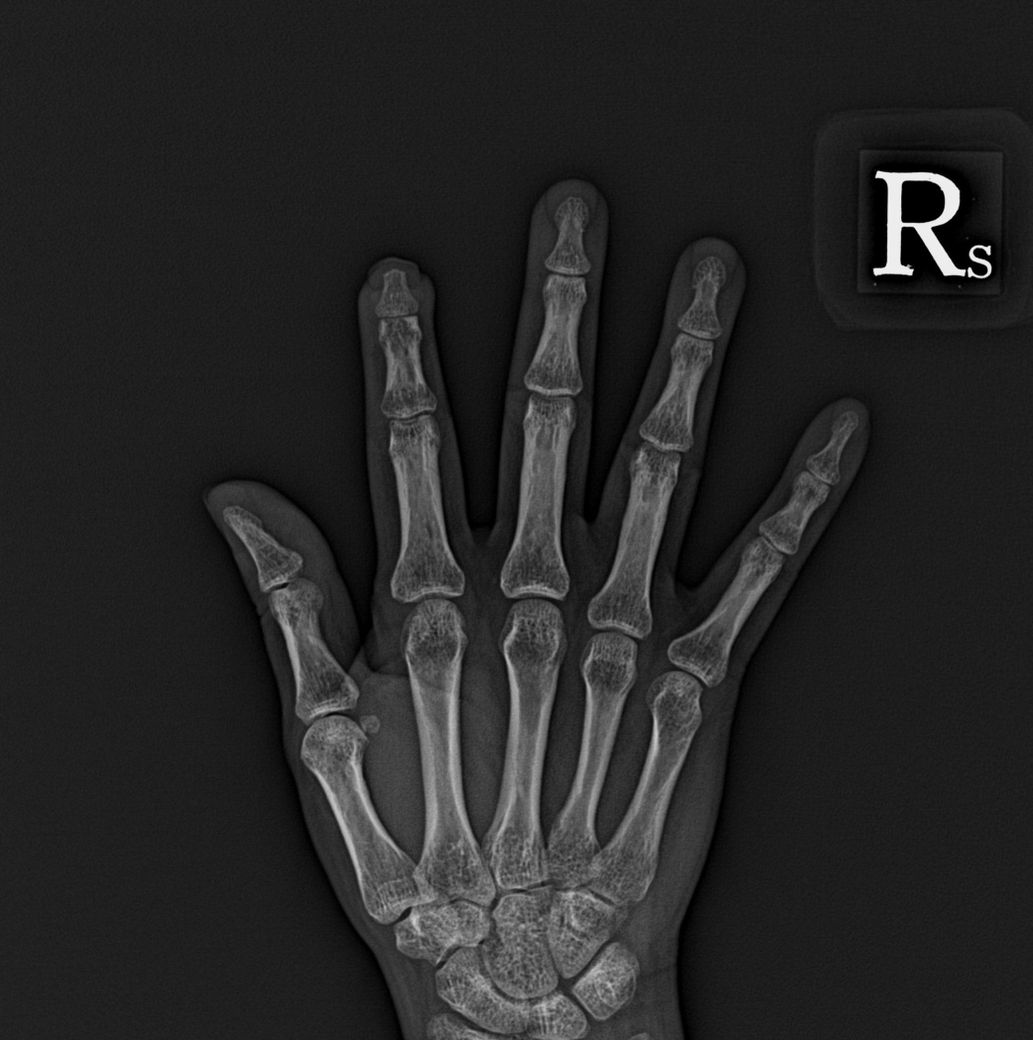

산재장해등급 관련 문의드립니다..

상병명

우 2수지 첨부절단 (원위지골 골절 포함)

재접합수술(원위지골단축 및 금속핀고정술, 수지동맥 봉합, 조상봉합) 시행.

첨부 괴사로 핀제거 및 괴사조직 절제, VY전진피판술, 조갑성형술 시행.

산재 장해등급이 몇급이 나올까요?

장해등급은 운동가능영역에 따라 판단하여야 합니다.

질의의 치료 내용과 사진만으로는 판단이 어렵고, 의료기관의 진단 및 실제 운동가능영역에 관한 자료가 필요합니다.